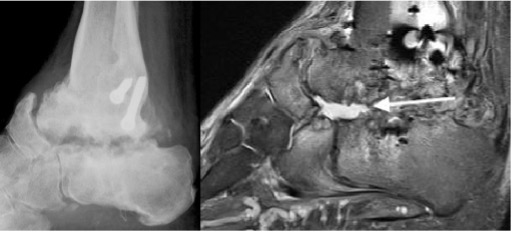

Infected nonunion subtalar joint (arrow)